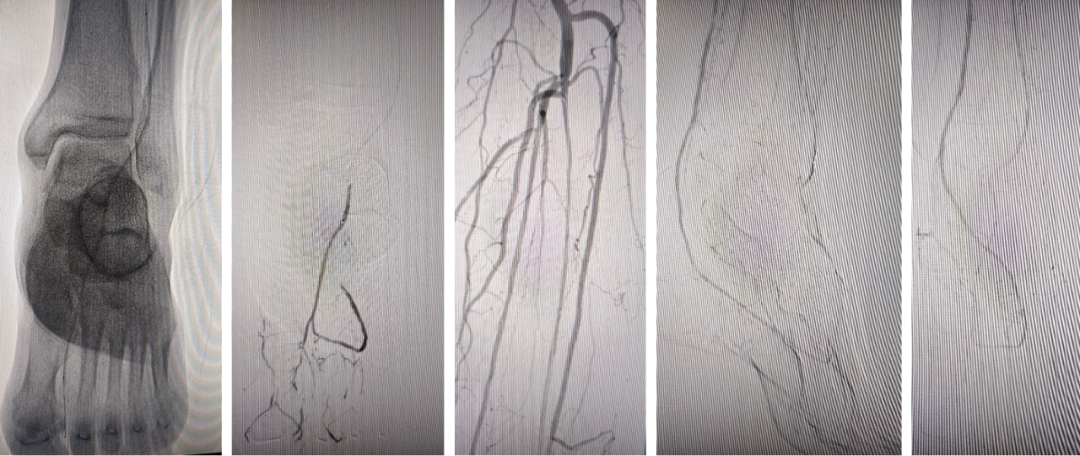

★ 足底外侧动脉的关键作用

Case 9:患者第三、四足趾不愈合,造影显示胫后动脉存在但足底外侧动脉缺如,足底内侧动脉不供应外侧足趾。术者开通胫前动脉后,经足弓将导丝送入足底外侧动脉进行扩张,最终实现足趾愈合。此病例提醒:足底弓的完整性不仅要看主干,还要关注分支动脉的供血范围。